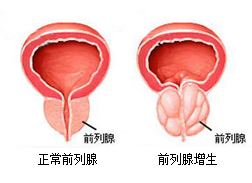

前列腺增生是“谁”引起的?

前列腺增生是谁引起的?前列腺增生疾病,是一种男性到了 中老年时期 容易发生的疾病。伴随着年龄的增长,疾病的发病率也呈上升趋势。前列腺增生严重危害着患者的身体。老年人...[详细]

【前列腺增生】

【前列腺增生】